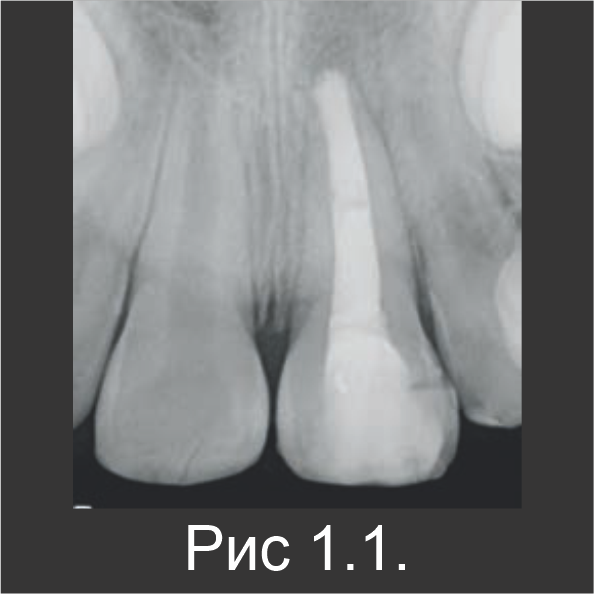

Апексогенез

У 7-летнего мальчика произошел осложненный перелом коронки зуба 21. Это произошло во время занятий спортом (рис. 3.1). В зубе 21 наблюдалась чувствительность к перкуссии, а пульпа была открытой. Пациенту ввели местный анестетик, а участок перелома очистили промыванием физиологическим раствором. Непосредственно на открытую пульпу нанесли Biodentine™, который также оставили в качестве временной пломбы (рис. 3.2).

Спустя четыре недели поверхностный слой Biodentine™ удалили высокоскоростным алмазным бором с водяным охлаждением и заменили композитной реставрационной конструкцией. Во время второго посещения пациент уже не жаловался на чувствительность. После первого посещения жалоб на боль не было. Признаки патологии на рентгенограмме отсутствовали. Во время контрольного обследования обнаружили симметричный апексогенез обоих центральных резцов (рис. 3.3).